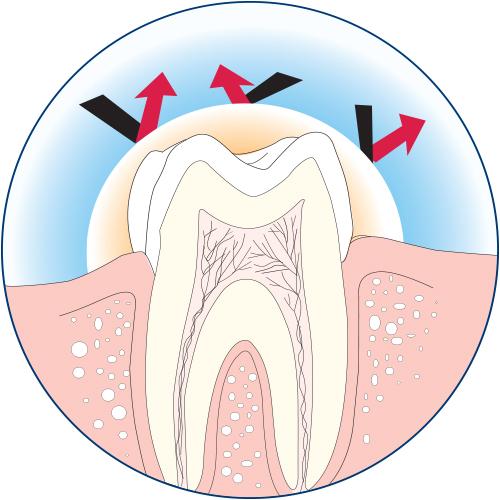

For over 50 years, Cetacaine has been trusted by dentists and hygienists to deliver effective and rapid pain control where it is needed, and can help put nervous patients at ease. Our unique formula combines three active ingredients to provide a rapid onset of 30 seconds with the benefit of a long duration of up 60 minutes, when used as directed. Cetacaine is indicated for use on all accessible mucous membrane, except the eyes.

For over 50 years, Cetacaine has been trusted by dentists and hygienists to deliver effective and rapid pain control where it is needed, and can help put nervous patients at ease. Our unique formula combines three active ingredients to provide a rapid onset of 30 seconds with the benefit of a long duration of up 60 minutes, when used as directed. Cetacaine is indicated for use on all accessible mucous membrane, except the eyes.